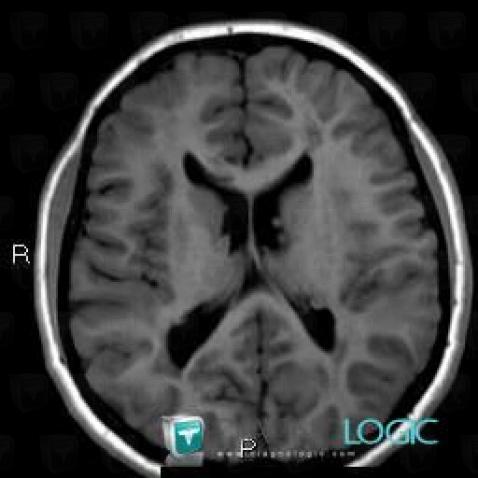

Here is the specific information in the key image above:

- Diagnosis Tuberous sclerosis (link to Hamartoma), Location(s) Ventricles / Periventricular region, with gamuts Periventricular anomaly seen in MRI, Ventricular wall nodules

Here is the specific information in the key image above:

- Diagnosis Tuberous sclerosis, Location(s) Ventricles / Periventricular region, with gamuts

- Diagnosis Hamartoma, Location(s) Ventricles / Periventricular region, with gamuts Periventricular anomaly seen in MRI, Ventricular wall nodules